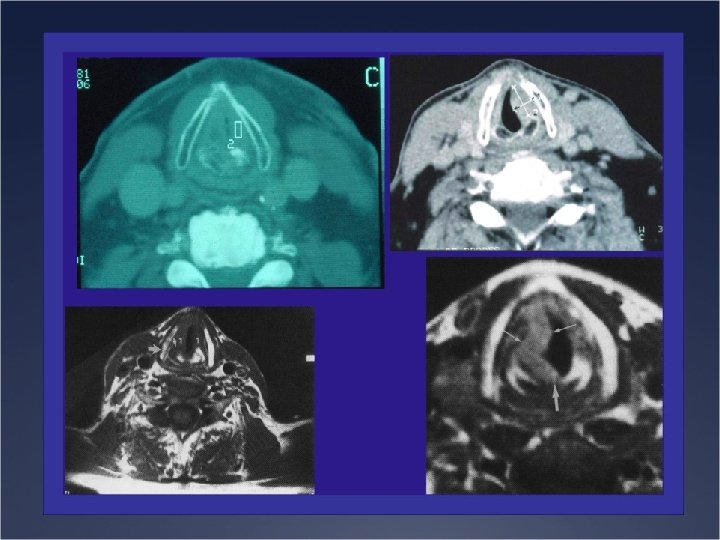

Examens Complémentaires Ü Morphologie Ü Pan endoscopie Ü TDM cervical ou IRM (thyroïde) Pathologie

Examens Complémentaires Ü Morphologie Ü Pan endoscopie Ü TDM cervical ou IRM (thyroïde) Pathologie tumorale laryngée Ü Mécanique Ü Stroboscopie des cordes vocales Ü TDM Ü EMG laryngé Ü Pan endoscopie Lésion fonctionnelle ou immobilité